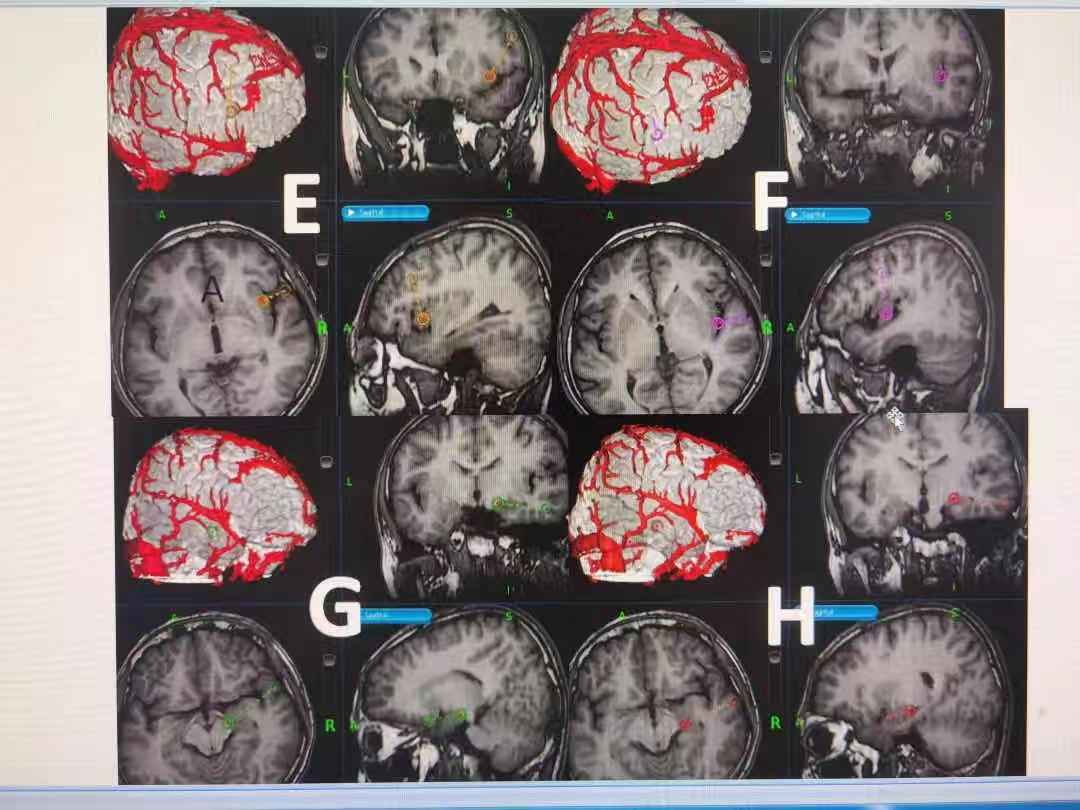

刘仕勇教授指出,难治性癫痫的外科治疗,通常包括手术切除病灶、迷走神经电刺激术以及SEEG引导下射频热凝毁损。目前外科手术切除癫痫病灶仍然是治疗难治性癫痫的首选方式。专家强调指出,要想将癫痫治愈就需要把异常放电的癫痫灶找到并切除掉,而目前常用的皮层脑电图只能从一个表面推测病变部位,无法精准监测到病灶位置,此外,脑部神经错综复杂一旦伤及其他神经元,后果不堪设想,而先进的立体定向脑电图技术(SEEG)能很好避开脑血管及重要脑功能区,通过微创外科手术,将电极放入大脑深部,全面监测癫痫的起源、扩散和症状产生,构建3D的“癫痫网络”,为癫痫外科手术提供更加精准、立体、完整的定位。

在经过全面的检查和详细了解孩子的病史后,专家决定为其进行SEEG检查。检查中,专家通过磁导航和术中脑电图引导,根据癫痫病灶的提示经皮精准插入9根电极针,通过这9根电极针对王鑫的癫痫病灶进行精准的3D定位,从而为毁损病灶提供更加精准的指引。

刘仕勇教授介绍,通过这种目前临床最新检查手段,一方面能为癫痫的外科手术治疗提供更精准的指引,另一方便还能在手术中有效保护大脑功能区,避免手术对大脑功能的损伤。特别是通过该检查,对于一部分癫痫病灶较小、波及范围局限的癫痫患者可以直接选择热凝治疗。从目前初步检查结果看,王鑫将有机会接受不开颅治癫痫的最新治疗方式。